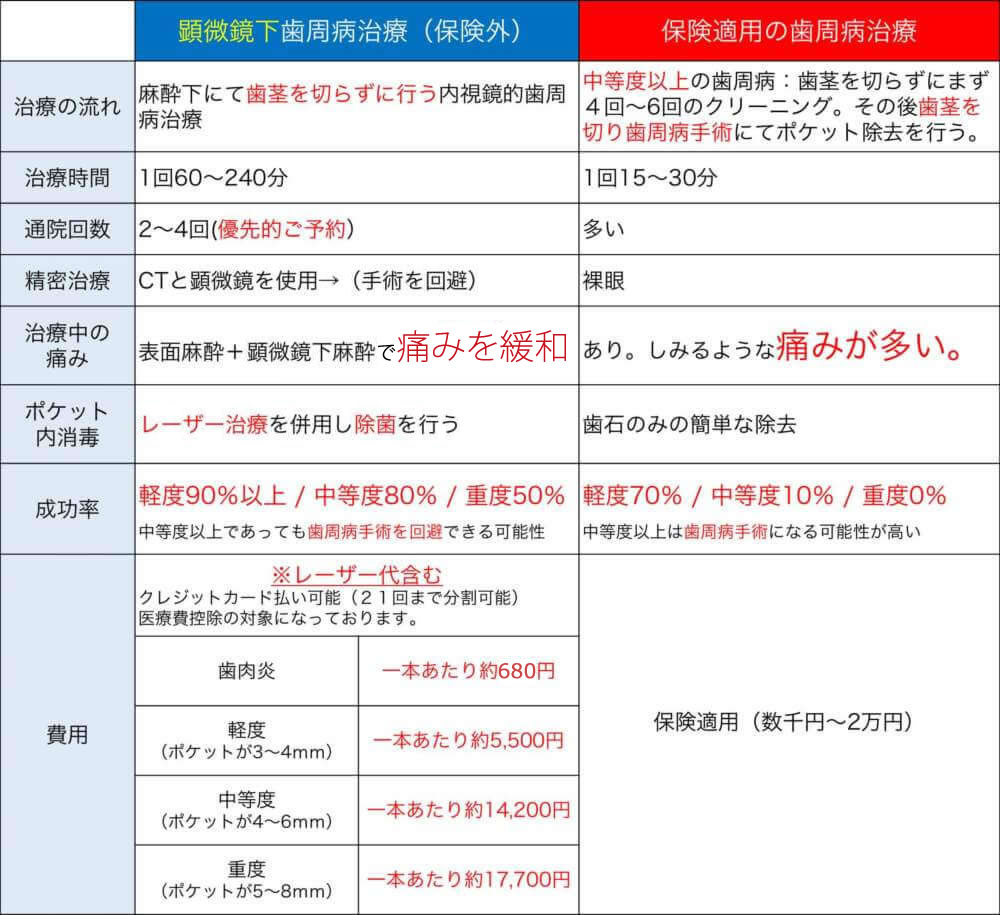

⑨ 歯周病治療の費用

保険診療、自由診療の歯周病治療によって、また、軽度、中等度、重度歯周病といった症状によって、費用・治療内容に差があります。

▼クリックで拡大します

| 名称 | イメージ | 特性 | 料金(税込) |

|---|---|---|---|

| 保険診療 |  |

状態に関わらず保険適用にて治療 |

数千円~2万円程度 |

| 自由診療(歯肉炎治療) |  |

歯周ポケットが2mm以下 |

約680円 / 1歯あたり |

| 自由診療(軽度歯周病治療) |  |

歯周ポケットが3~4mm | 5,500円 / 1歯あたり |

| 自由診療(中等度歯周病治療) |  |

歯周ポケットが4~6mm | 14,200円 / 1歯あたり |

| 自由診療(重度歯周病治療) |  |

歯周ポケットが5~8mm | 17,700円 / 1歯あたり |